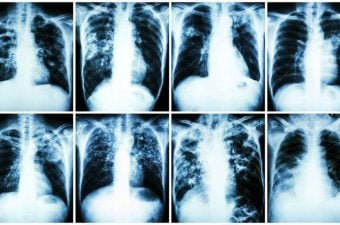

Tabaquismo pasivo

Ya está comprobado que tabaquismo pasivo puede provocar las mismas enfermedades del tabaquismo activo. Por lo tanto, las leyes antitabaco, cada vez más restrictivas en todo el mundo, son no sólo una cuestión de no fumadores molestados con el olor del humo de los fumadores. Es una cuestión de salud personal y pública.

Cánceres de pulmón en no fumadores no son muy comunes, pero la mayoría afecta a las personas que viven en la misma casa de un fumador. El 90% de los cánceres de pulmón ocurren en fumadores; el 10% restante son en gran parte con los fumadores pasivos. Un no fumador casado con un fumador tiene 20% más de probabilidades de morir de cáncer de pulmón y enfermedades cardiovasculares que los no fumadores no expuestos al tabaquismo pasivo. Los no fumadores que viven con fumadores tienen una mortalidad hasta un 15% más grande que las personas sin contacto frecuente con el cigarrillo.

Hijos de padres que fuman, expuestos al tabaquismo pasivo intradomiciliario por al menos 25 años, tienen el doble de probabilidad de desarrollar cáncer de pulmón.